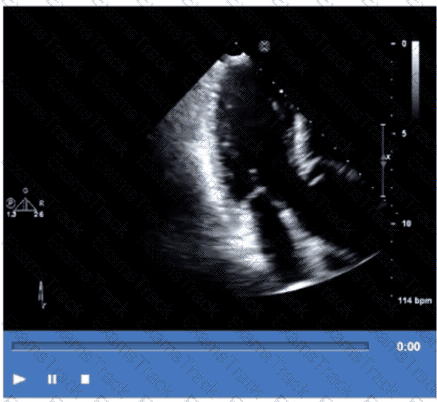

Which finding is best demonstrated in this video?